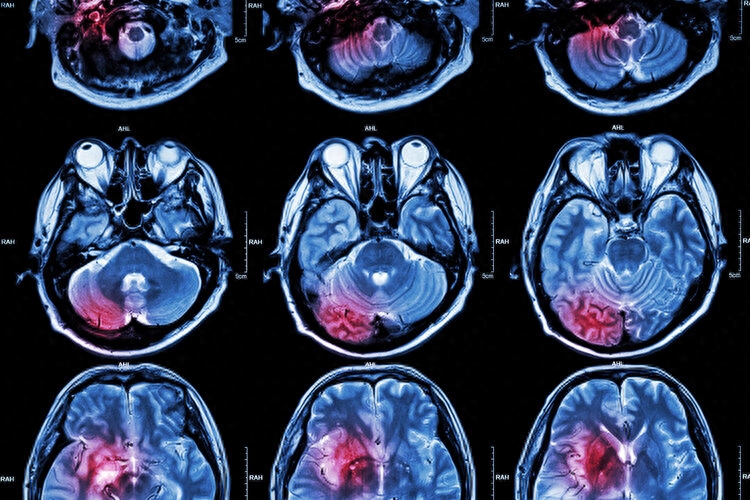

經頭顱CT檢查,李叔被診斷為腦出血,而且出血量較多,情況十分危急,還好手術后,李叔脫離了危險期。

所謂腦出血,就是出血性腦卒中,是腦卒中(中風)的一種。發病率佔到全部腦卒中疾病的20%-30%,急性發作期的致死率高達30%到40%。腦出血好發於40-65歲年齡段,並且發病率會隨著年齡增加而提升。

大部分的腦出血是由於大腦內硬化的小血管破裂而致。長期的高血壓讓血管壁變得十分薄脆,血壓一旦突然升高,血管就會破裂,導致腦出血。因此,腦出血又被稱為「高血壓性腦出血」。